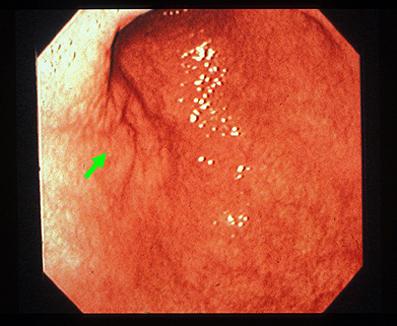

症例提示(所在地,施設名等): 愛知県・ 愛知県がんセンター

TIC症例

疾患(病理主体)の分類悪性上皮性腫瘍/腺癌

部位(臓器別)胃(部位)/2つ以上

検査方法内視鏡

腫瘍の肉眼分類4型(びまん浸潤型)/

病変の最大径(ミリ)40以上

腫瘍の深達度ss(a1)

多発腫瘍(同一臓器)